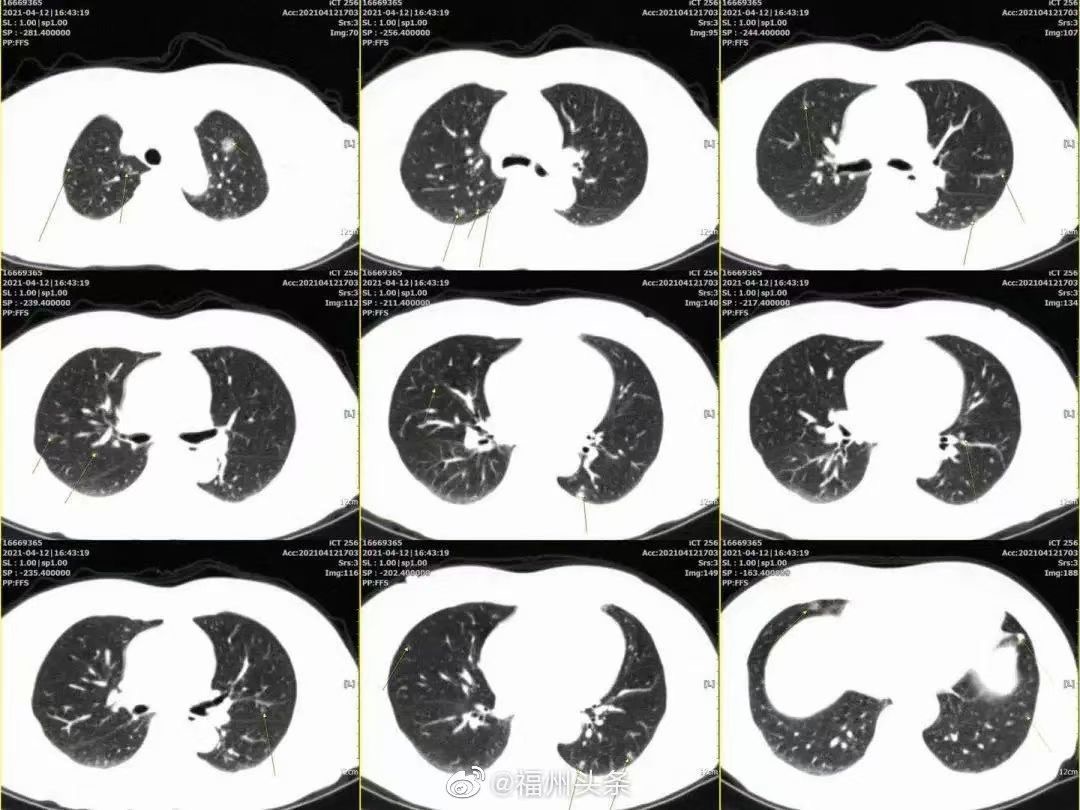

照(zhào)CT后医(yī)生震惊:女(nǚ)子双肺长出20多(duō)个(gè)结节!与这一习惯(guàn)有关.....

肺(fèi)部长(zhǎng)有结节并不(bú)稀奇,可罕见的是,福(fú)州60多岁的王(wáng)女士竟查出双肺同(tóng)时存(cún)在20多个结节(jiē)。看(kàn)到王女士的(de)CT片(piàn)子后(hòu),“身经百战(zhàn)”的医生(shēng)都(dōu)大吃一(yī)惊,而且根据结节大小来(lái)判断,其中十几个还与肺(fèi)癌有相(xiàng)关性。

专家团队(duì)综合(hé)评估情况后一致认为王女士大(dà)部分结节属(shǔ)于早期(qī),早日切除能争(zhēng)取(qǔ)更大的生存机会,如(rú)任(rèn)其(qí)自由(yóu)发展,那么(me)一般情况下三年之(zhī)内生存率将低于20%。

但这20多(duō)个肺结节(jiē)就像是“地(dì)雷(léi)”一样分布在她的每个肺叶上,如果(guǒ)要全部解决,几乎要将肺叶(yè)全部切(qiē)除,这会让王女士今后的生活质(zhì)量大大降低。而一(yī)些结节位置不(bú)好定位(wèi),也加大(dà)了手术难度。到底是切(qiē)除肺叶“一刀(dāo)两(liǎng)断”,还是“各个击破(pò)”成了摆在(zài)专(zhuān)家团队面前的问题。经过再(zài)三思量,心胸外科专家团队针对结节大小和部位(wèi),制定了(le)治疗方案。